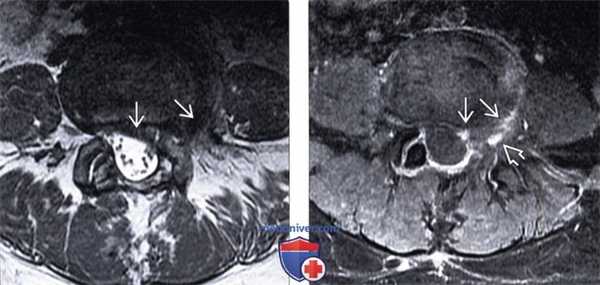

(Слева) Т1-ВИ, аксиальный срез: крупное мягкотканное образование, сообщающееся с межпозвонковым диском L4-L5 и распространяющееся в правое межпозвонковое отверстие и экстрафораминальные мягкие ткани.

(Справа) Т1-ВИ, сагиттальный срез: крупная латеральная и фораминальная грыжа диска, замещающая собой фораминальную жировую клетчатку и смещающая корешок L4 вверх.

(Слева) Т2-ВИ, аксиальная проекция: экструзия диска на широком основании, распространяющаяся у данного уже прооперированного пациента из левой парацентральной области в левое межпозвонковое отверстие.

(Справа) На аксиальном Т1-ВИ с КУ представлен случай рецидивирующей фораминальной грыжи: отмечается легкое контрастное усиление сигнала, окружающее крупную левостороннюю и фораминальную грыжу диска.